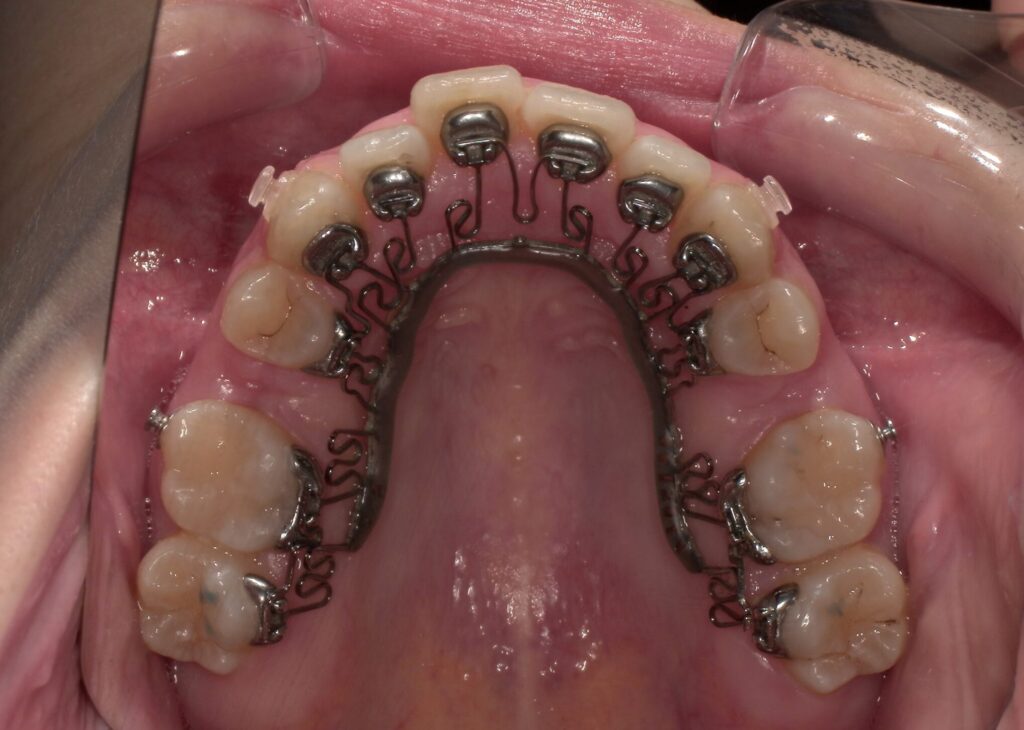

📸治療経過写真

当院で裏側矯正治療しているスタッフの経過写真をご参考にしてください。

上下左右小臼歯を1本ずつ計4本抜歯して現在も治療中です。「歯を抜いた隙間が閉じた量」、「前歯の移動量」、「正面から見た前歯の位置」に注目して見てもらえると、歯の移動の早さが目に見えて分かるかと思います。

約4か月後

上顎